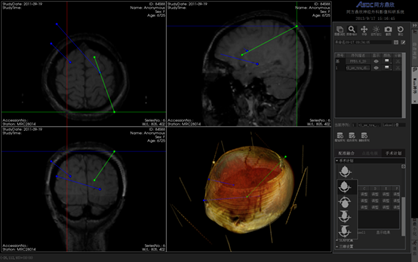

同方鼎欣專業影像產品群是直接面向神經外科、骨科、血管分析等臨床科室的輔助診療、手術計劃、分析的解決方案,系統整合了醫療影像的導入、二維閱片、三維重建、序列配準融合、自動分割、自動計算、手術計劃等一系列功能。充分滿足了臨床科室的專業需求,提供了完整、強大、可靠、方便的工具平臺。

三維體繪制重建(VR)、三維面繪制重建(SR);

神經外科手術規劃模塊;